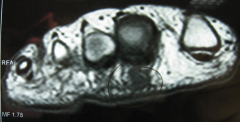

Νεύρωμα Morton όπως φαίνεται στη μαγνητική τομογραφία